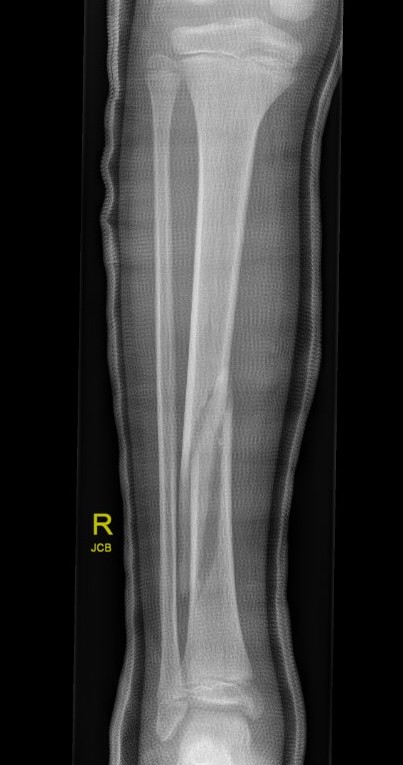

Proximal Metaphyseal Tibial Fracture / Cozen's Fracture

Issue

- may develop long term valgus alignment

- due to medial epiphyseal overgrowth / periosteum medially

Management

Any displacement

- MUA

- extension long leg cast with varus mould